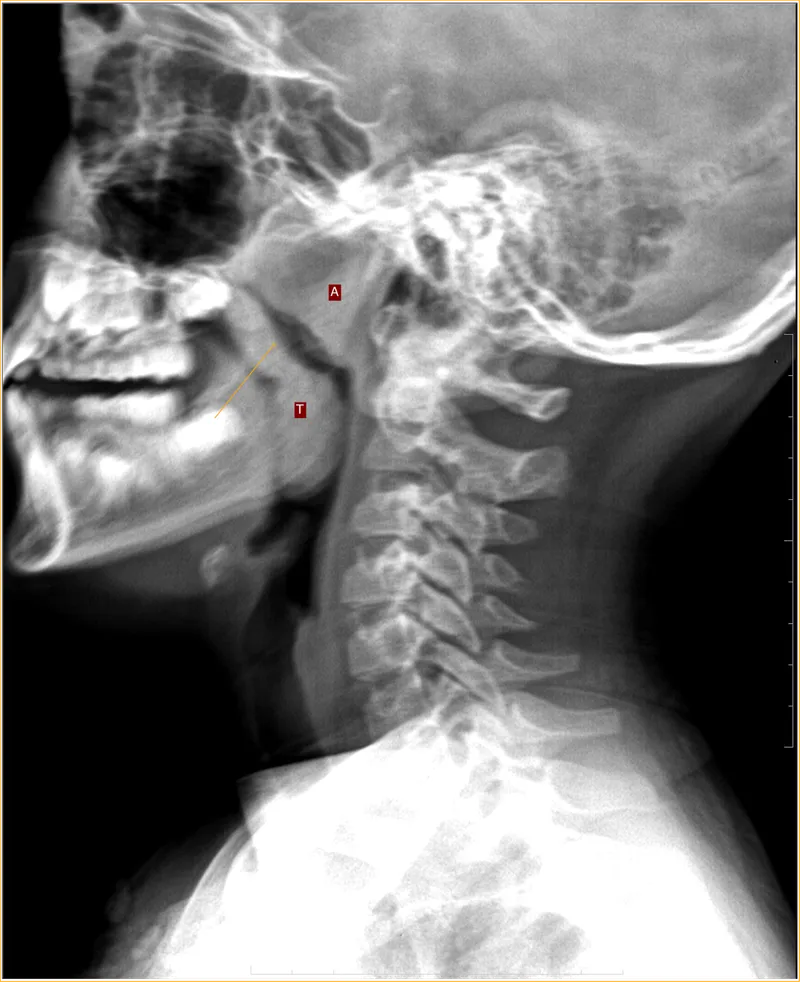

- X-ray Soft Tissue Lateral Neck View: Assesses adenoid size relative to nasopharyngeal airway. Narrowed airway; >50% obstruction significant. Calculates Adenoid-Nasopharyngeal (A/N) ratio.

⭐ Nasal endoscopy is the gold standard for diagnosis, but X-ray soft tissue lateral view of nasopharynx is a common, non-invasive investigation.

- Diagnosis often clinical; X-ray lateral neck view (soft tissue) can confirm.